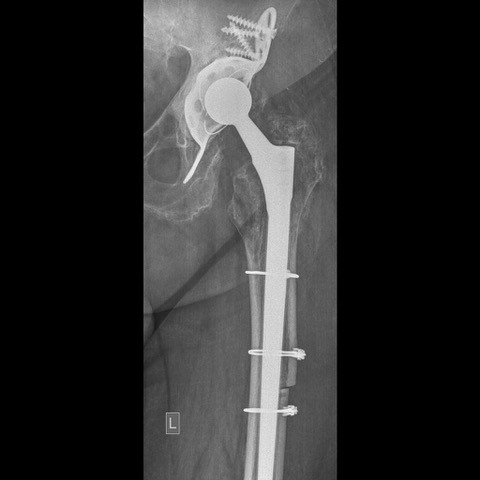

Πρόκειται για επεμβάσεις αναθεώρησης/revision των αρθροπλαστικών με τις οποίες γίνεται αφαίρεση μέρους ή όλων των αρχικών προθέσεων και αντικατάσταση με καινούργιες προθέσεις.

Κάθε περίπτωση έχει ιδιαιτερότητες που σχετίζονται με το είδος της αρθροπλαστικής που πρέπει να αναθεωρηθεί, με τον τρόπο που θα αφαιρεθούν οι παλιές προθέσεις, με την τεχνική κάλυψης των οστικών ελλειμάτων που συνήθως υπάρχουν στην περιοχή, με τον τρόπο που πρέπει να στερεωθούν τα καινούργια υλικά, με τον χειρισμό των μαλακών μορίων κ.α.

Στις περισσότερες περιπτώσεις η επέμβαση αναθεώρησης των αρθροπλαστικών δεν έχει καμία σχέση με τις τεχνικές και τα υλικά που χρησιμοποιούνται στις αρχικές αρθροπλαστικές.

Η απαραίτητη εμπειρία της χειρουργικής ομάδας που χειρίζεται αυτές τις δύσκολες περιπτώσεις πρέπει να συνδυάζεται με την χρήση σύγχρονων υλικών.

Η χρήση όμως των σύγχρονων τεχνικών και προηγμένων υλικών επιτρέπουν συνήθως μετεγχειρητικά την γρήγορη και ασφαλή κινητοποίηση.